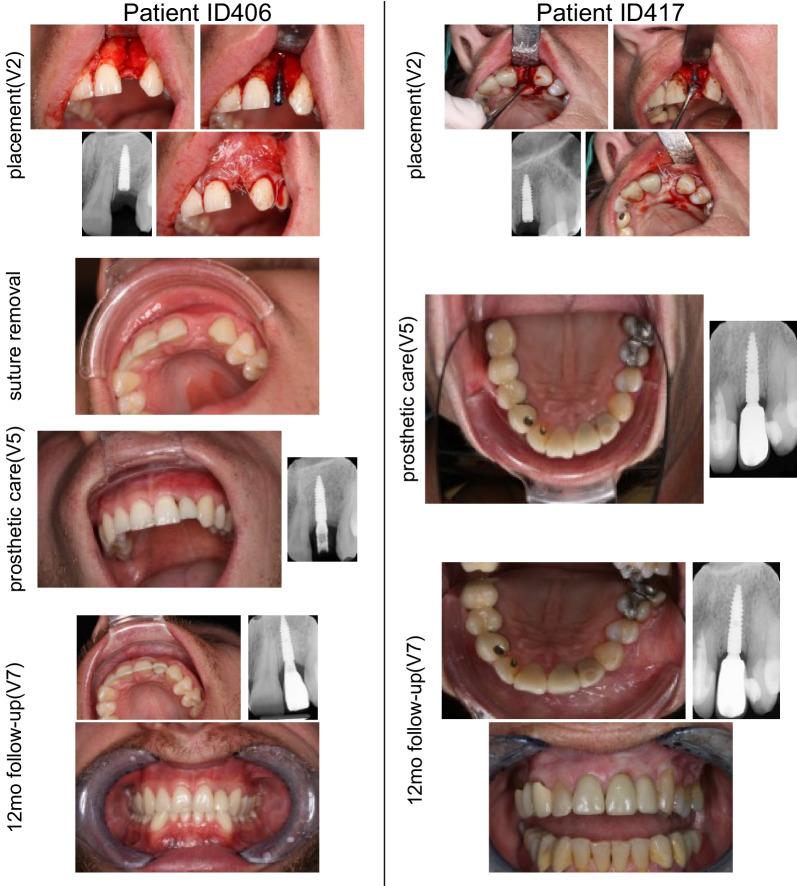

All surgeries were performed according to instructions and no complications were reported. Study implants were mainly placed at FDI position 12 (18 patients; 43.9%) and 22 (17 patients; 41.5%). 14 cases (34.1%) required a simultaneous bone augmentation procedure. Lateral and contour augmentation was done in 10 (71.4%) and four (28.6%) cases, respectively. In 11 cases (78.6%), a resorbable collagen membrane was used. The inserted implants were either 10 mm (24.4%; n = 5), 12 mm (78%; n = 32) or 14 mm (9.8%; n = 4) in length. The bone quality was assessed as type II (24.4%; n = 10), type III (65.9%; n = 27), or type IV (9.8%; n = 4). Tapping was regarded as not applicable in 75.6% of the patients due to bone quality type III/IV. Primary stability was achieved in 40 out of the 41 patients (97.6%). The further course of the unstable implant was uneventful, and a provisional crown could be installed according to the study protocol. The implants healed submerged in 80.5% (n = 33) and transgingival in 19.5% (n = 8). The suture was removed in all patients, and 29 patients received a provisional crown and a final crown. The representative surgical and follow-up pictures and X-rays are shown in Fig. 3. The distribution of implant sites and frequency of bone augmentation is presented in Table 2.

Fig. 3.

Surgical, follow-up and X-ray images of the representative clinical cases. Clinical and X-ray pictures were taken during implant placement, suture removal, prosthetic care, and 12-month follow-up for 2 representative patients